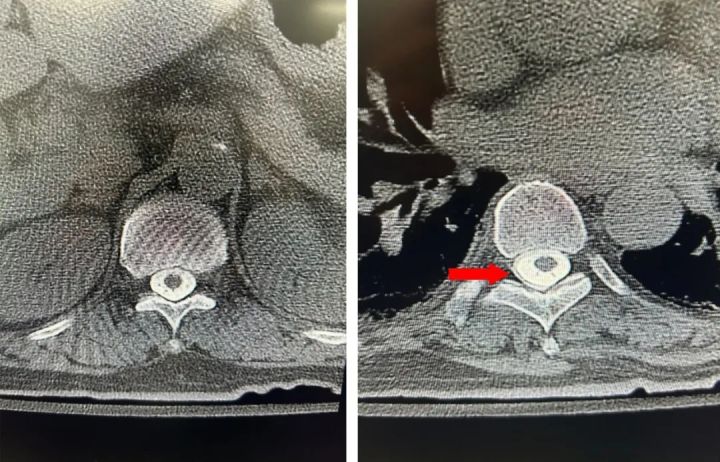

在向椎管内注射完造影剂后,徐航哲立即联系放射科,给老俞扫了个全脊柱薄层CT。

很快,层厚为0.6mm的薄层CT传上来了,一共有一千多张片子。医生们围坐在电脑边,一帧一帧地寻找着,生怕错过任何一个细节。

明确了漏口,接下来又该怎么治疗呢?应广宇不慌不忙地向老俞介绍起了自己的“绝活”——硬膜外血贴术。“明天我们就安排手术,局麻,微创,打个针,半小时左右。”